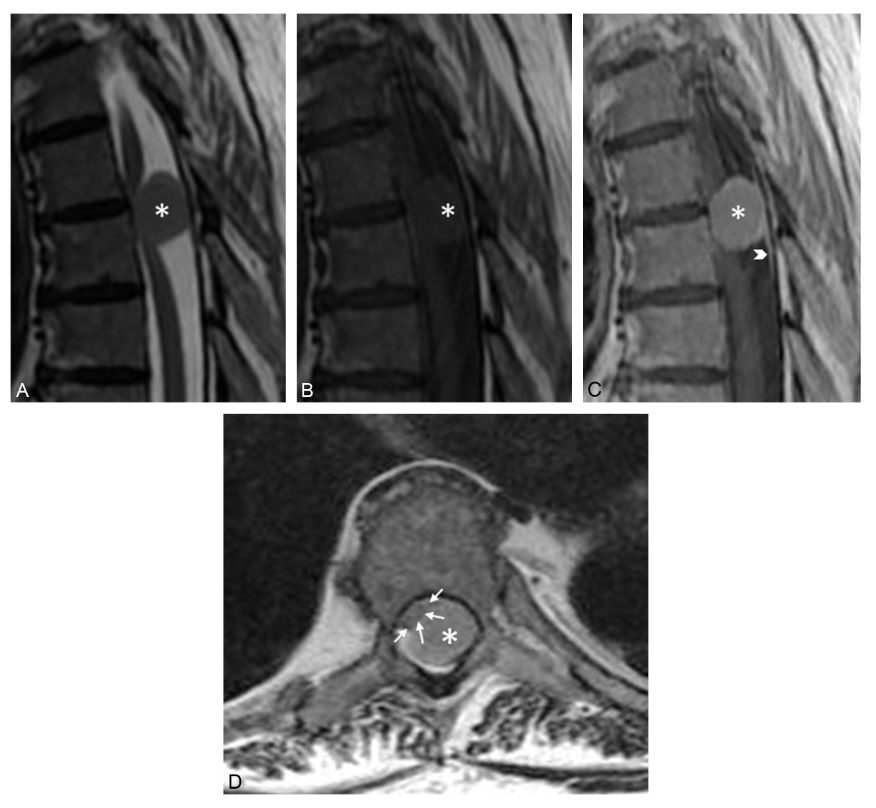

Fig. 52.4. Méningiome (cause intradurale extramédullaire).

IRM en coupes sagittales pondérées en T2 (A) et en T1, sans (B) et avec injection de gadolinium (C), et coupe axiale pondérée en T1 après injection (D). Masse à contours bien limités (∗) en isosignal en T2, en hyposignal en T1, prenant le contraste de façon intense et homogène et refoulant le cordon médullaire vers l’avant et vers la droite (flèches). Noter le raccordement méningé avec épaississement de la dure-mère, en « queue de comète » (tête de flèche).

Source : CERF, CNEBMN, 2022.